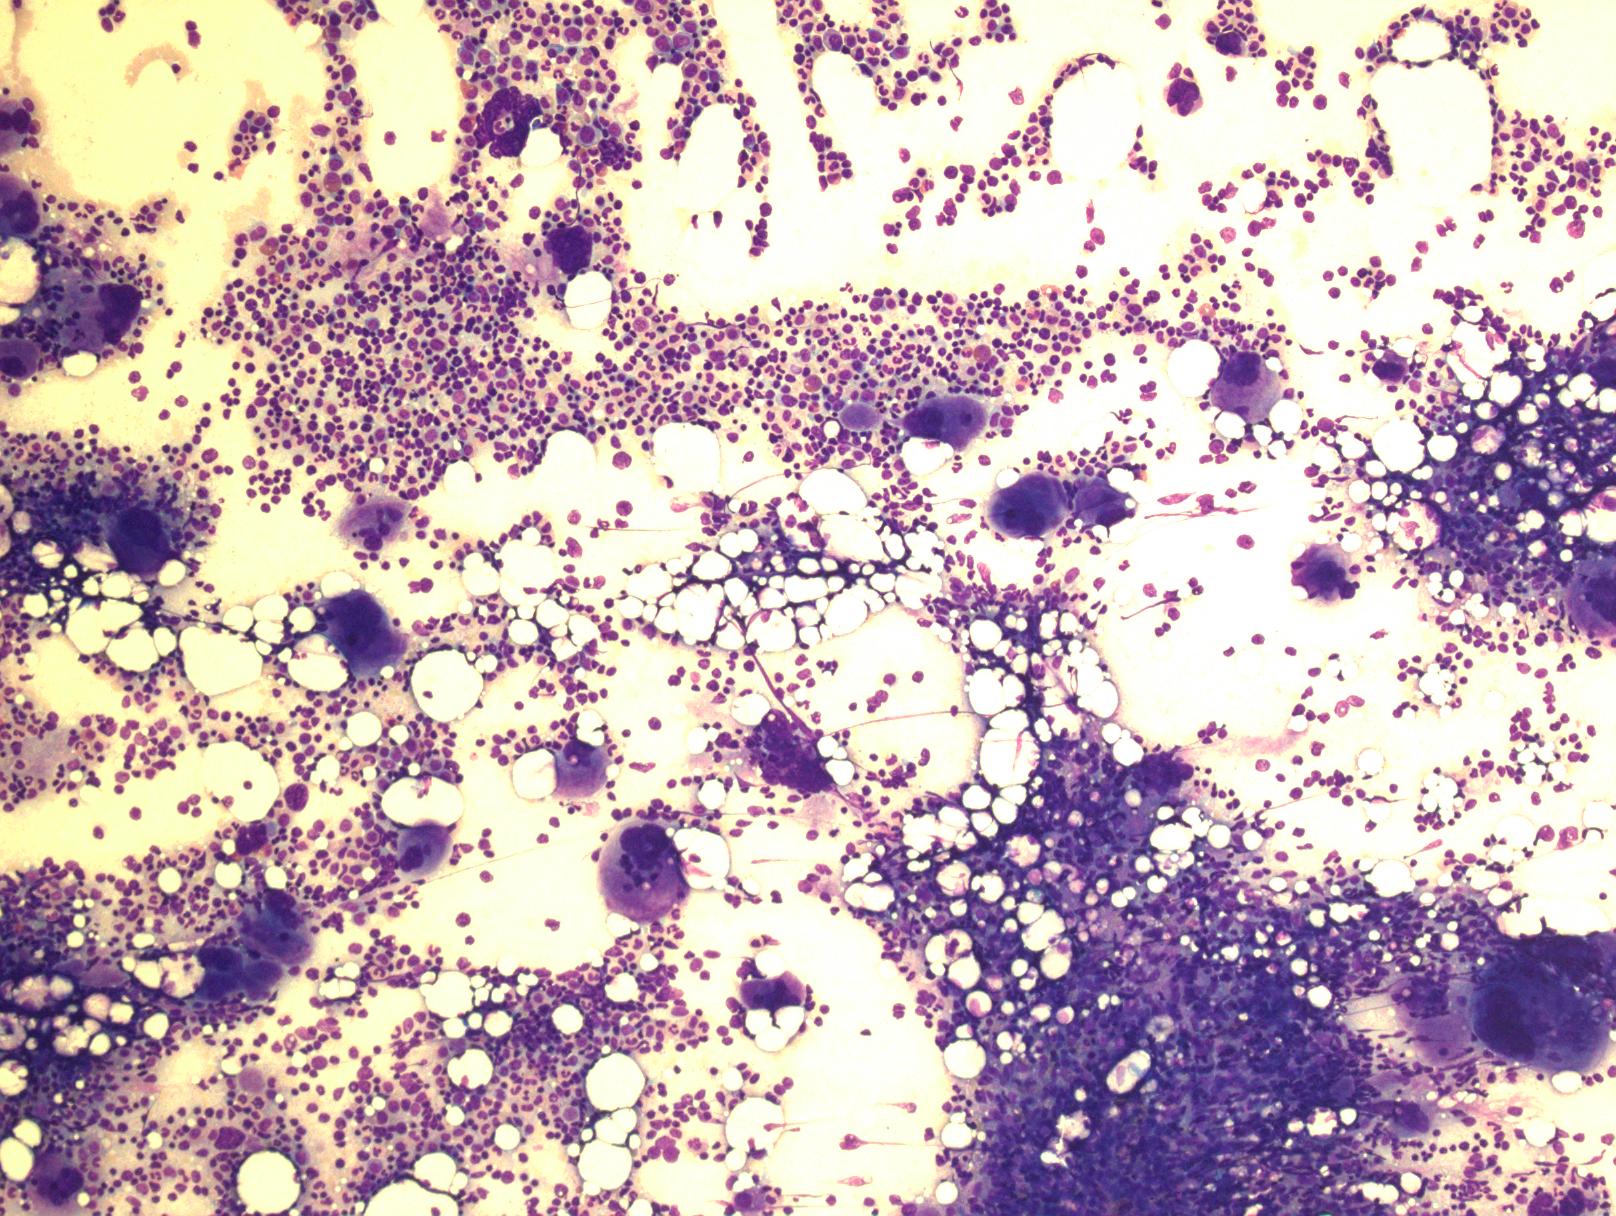

4. 骨髓细胞密度增加,特别是皮质旁细胞密度增加应值得重视。通常表现为全髓系增生,但以红系及巨核细胞增生为突出。特征性表现为:红系增生为正常红细胞,红系前体细胞呈大的岛状或片状分布。粒系增生形态正常,原始细胞不增多。巨核细胞数量增加,特别是血小板增多病例,常表现为多叶核。血小板增多、血红蛋白或红细胞压积较低病例早期骨髓表现和原发性血小板增多症相似。巨核细胞常形成松散的簇状或邻近骨小梁分布,细胞呈多形性,大小不一致,大多数巨核细胞核折叠正常或分叶深,缺乏明显异型,仅少数细胞核圆形或其它异常形态,特别是伴轻微网状纤维增多时。血窦扩张,常充满红细胞。特征性的骨髓组织学改变常可将 PV 区别于原发性血小板增多、原发性骨髓纤维化及反应性红细胞增多或血小板增多。80%病例网状纤维网正常,其余病例可有网状纤维增多,甚至轻-中度胶原纤维增生。初诊时即使轻度的网状纤维增多(I 级)也预示疾病可快速进展到 PV 后骨髓纤维化,因此骨髓活检很重要。超过 90%病例骨髓铁染色阴性。